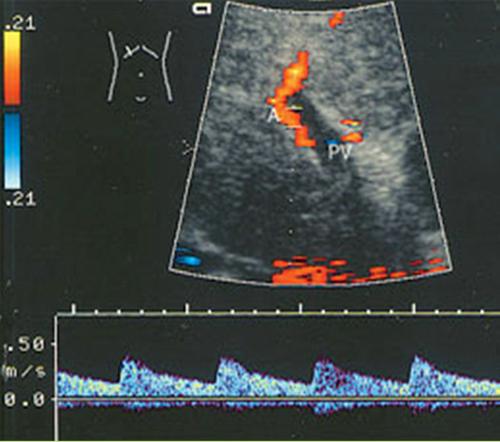

What is Portal venous hypertension?

This is an increase in portal venous pressure (above 10mmHg) or hepatic venous gradient (above 5mmHg).

What is the sonographic appearance of Portal venous hypertension?

Portal vein measures greater than 13mm

Collateral

circulation

Flow reversal

Ascites

Hepatosplenomegaly

What is Portal Venous Thrombosis?

Portal Venous Thrombosis

What is the sonographic appearance of Portal Venous Thrombosis?

Portal flow absence

echogenic thrombosis

Worm-like

structures near porta hepatis